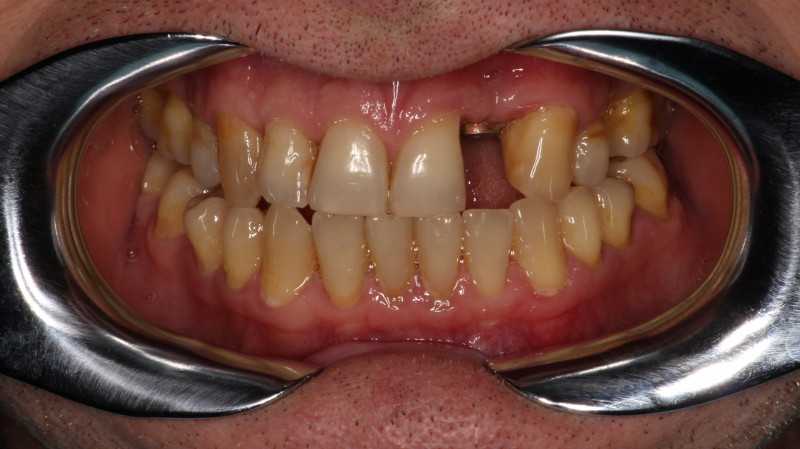

На странице представлено портфолио стоматологий Новосибирска с фото работ до и после имплантации зубов. Мы собрали разные клинические случаи: одиночные импланты, восстановление нескольких зубов и полная реконструкция зубного ряда. Здесь вы можете видеть, как выглядят восстановленные зубы, меняется форма улыбки после процедуры. Изучите результаты до и после имплантации зубов, чтобы оценить качество работы врачей и выбрать стоматологию в Новосибирске, которая поможет вернуть функциональность и эстетику вашей улыбке.

Жалобы: на отсутствие зубов, неудовлетворительную эстетику зубных рядов, невозможность жевать, снижение высоты прикуса. Что сделано: удаление зубов на в/ч и н/ч, установка имплантатов Bredent Sky и одномоментное протезирование акриловыми протезами с опорой на имплантаты по протоколу Fast & Fixed (зубы за один день). Через 8 месяцев проведена работа по замене протезов на постоянные металлокерамические. Что получил пациент: красивые и ровные зубные ряды, возможность нормально питаться с первого дня после операции, поднята высота прикуса, теперь не стесняется улыбаться.